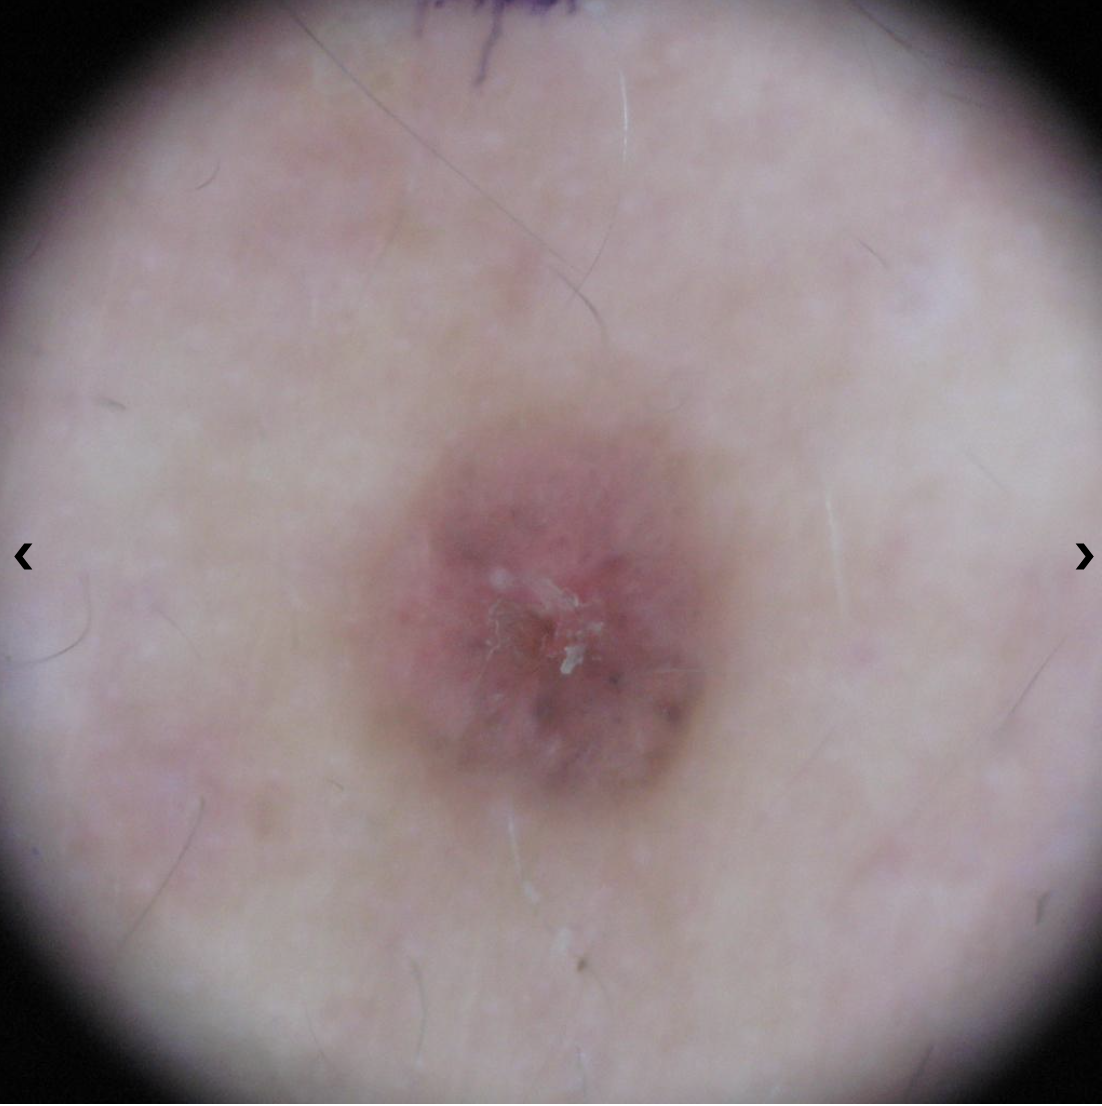

Basal Cell Carcinoma (BCC) Photos

Basal cell carcinoma on the posterior torso. Photo: International Skin Imaging Collaboration at isic-archive.com

Basal cell carcinoma on the neck. Photo: International Skin Imaging Collaboration at isic-archive.com

Basal cell carcinoma on the anterior torso. Photo: International Skin Imaging Collaboration at isic-archive.com

Basal cell carcinoma presenting as an open sore on the ear. Photo: International Skin Imaging Collaboration at isic-archive.com

Basal cell carcinoma presenting as a pink growth. Photo: International Skin Imaging Collaboration at isic-archive.com

Basal cell carcinoma on the leg. Photo: International Skin Imaging Collaboration at isic-archive.com

A small pink growth with a slightly raised, rolled edge and a crusted indentation in the center. (BCC)